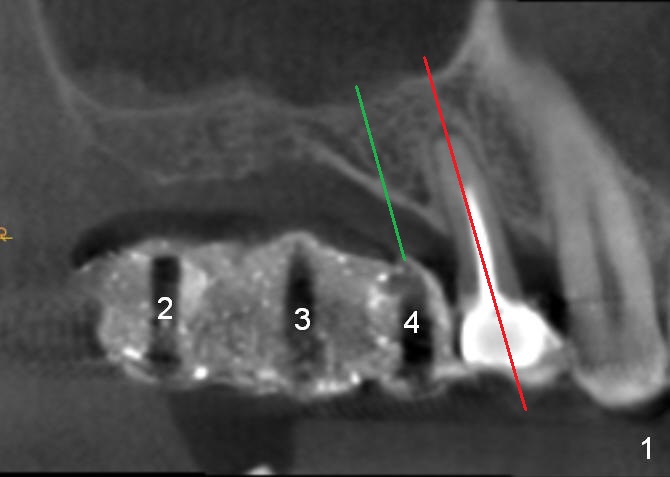

As mentioned earlier, the 56-year-old man is taking Plavix, one tablet every other day. The last time he took the medication is 4 days ago. For hemostasis, three carpules of 2% Xylocaine with 1:50,000 Epinephrine are administered in infiltration. Initial osteotomies are established through the CT scan stent (Fig.1-4: #2-4). Then an incision is made. After raising the flap, the osteotomy sites are checked. Ridge split is made between these sites with a chisel without much success. Bone is soft between #2 and 3. Sinus lift (Fig.2,4) is attempted at #2 and 4 (3.6 mm), whereas bone expansion is accomplished at #3, in the bone between the sinus (Fig.3 S) and the nasal cavity (N).

After use of 2.8 mm round bur at #4 for sinus lift, a 4x8.5 mm regular drill is used with resultant sinus membrane perforation at the sinus floor. The latter is repaired with insertion of Osteogen plug prior to place 4.5x8.5 mm implant (Fig.5,6). The similar mistake occurs at #3: after using 2.4/3.7 mm bone expander for 10 mm, a 4x10 mm is used, which also results in sinus perforation, probably sideway, buccally. Trimmed Osteogen plug is placed before a 4.5x10 mm implant is placed with primary stability (Fig.6). The reason for use of the regular drills is to avoid ridge fracture due to under prep.

Since the bone at #2 is soft, the 3.6 mm round drill is used after 2.8 mm one. When a 5x8.5 mm implant is placed, there is no ridge fracture. The implant at #2 should have been placed more distal (Fig.6 arrow).

Insertion torque of the three implants is ~ 50 Ncm. Three long (because of severe vertical bone resorption (Fig.1,6)) abutments are placed immediately for immediate splinted provisional (Fig.7,8 P). The latter should have hemostatic effect. Application of peridontal dressing (D) has additional hemostatic function, exerting pressure the most anterior (Fig.7 between the teeth #5,6) and the most posterior (Fig.8 arrow) incision, where the provisional cannot. Sulcus incision is good to remove subgingival calculus. It seems that chronic periodontits and bruxism play roles in pathogenesis of bone loss.